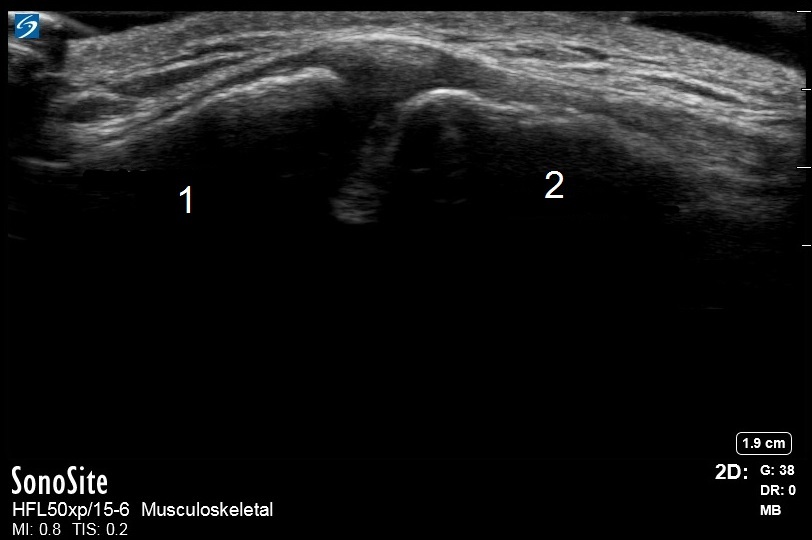

Imagen de la articulación acromioclavicular normal del hombro

Acromion

Clavícula